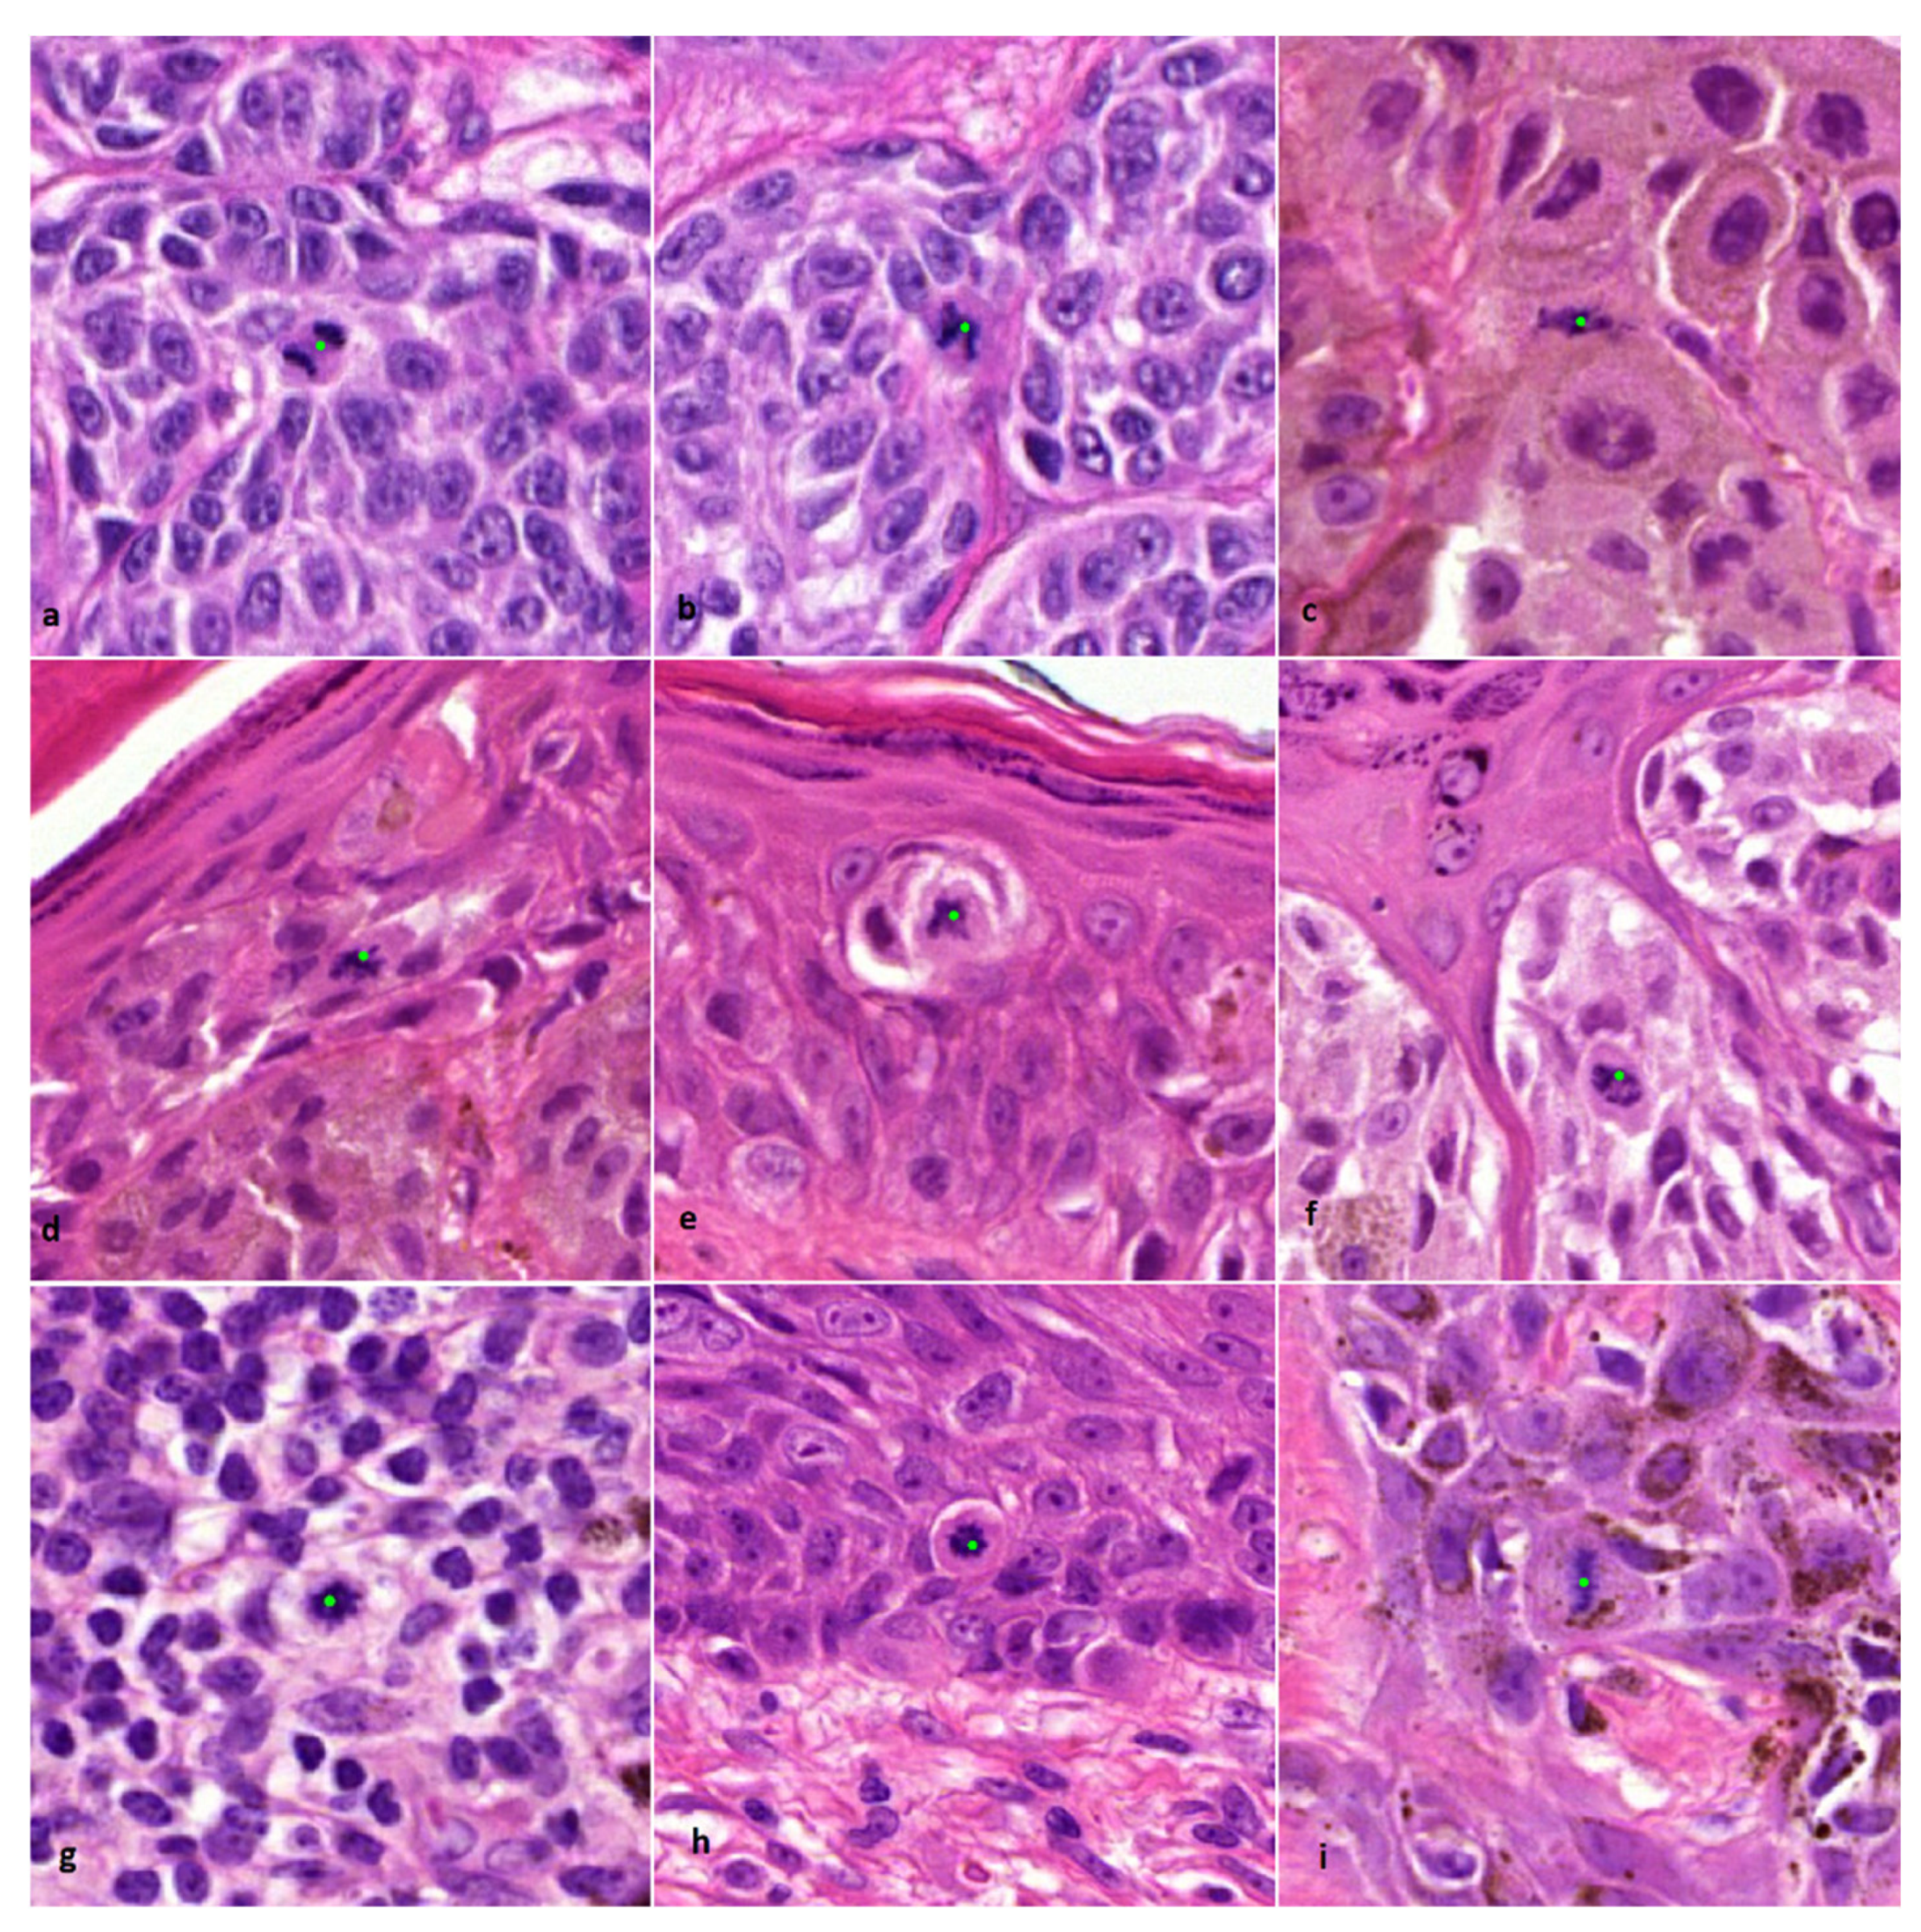

- Andres, C.; Andres-Belloni, B.; Hein, R.; Biedermann, T.; Schape, A.; Brieu, N.; Schonmeyer, R.; Yigitsoy, M.; Ring, J.; Schmidt, G.; et al. iDermatoPath—A novel software tool for mitosis detection in H&E-stained tissue sections of malignant melanoma. J. Eur. Acad. Dermatol. Venereol. 2017, 31, 1137–1147. [Google Scholar] [CrossRef]